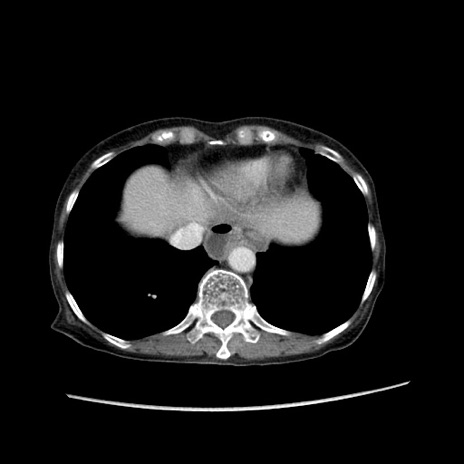

症例25(横断像)

【症例】80歳代女性

【主訴】胸のつかえ感

【現病歴】約9時間前に食後から胸のつかえた感じあり、嘔吐あり、来院。

【既往歴】胃癌(全摘)、胆摘、虫垂炎

【身体所見】心窩部に圧痛あり、反跳痛なし。

【データ】WBC 5700、CRP 0.05